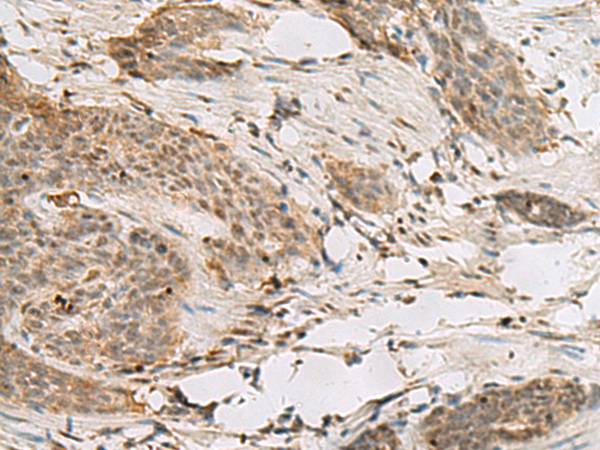

ELISA, IHC

IHC positive control:

Human tonsil and Human esophagus cancer

IHC Recommend dilution:

30-150